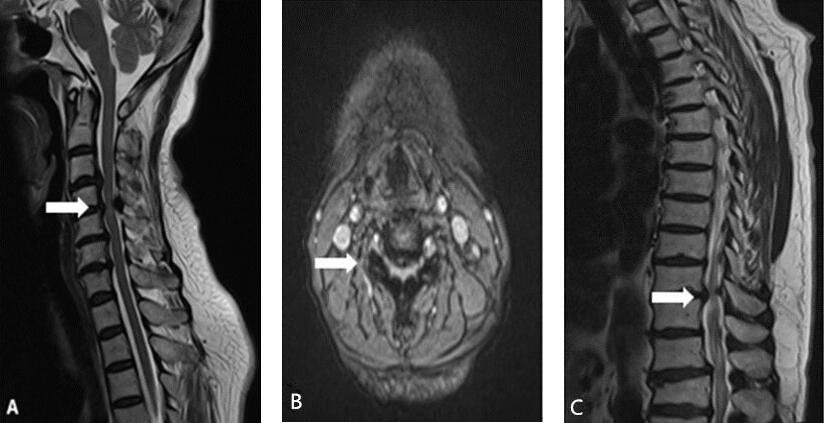

t2wi 可见继发于椎间盘脱出的脊髓受压,脊髓水肿或脊髓软化

行颈段mri检查,可见脊髓水肿明显(图2a,全脑dsa可见左侧椎动脉发出

颈胸腰多节段椎管狭窄一例(脊柱脊髓系列二十-浙二神外周刊(第222